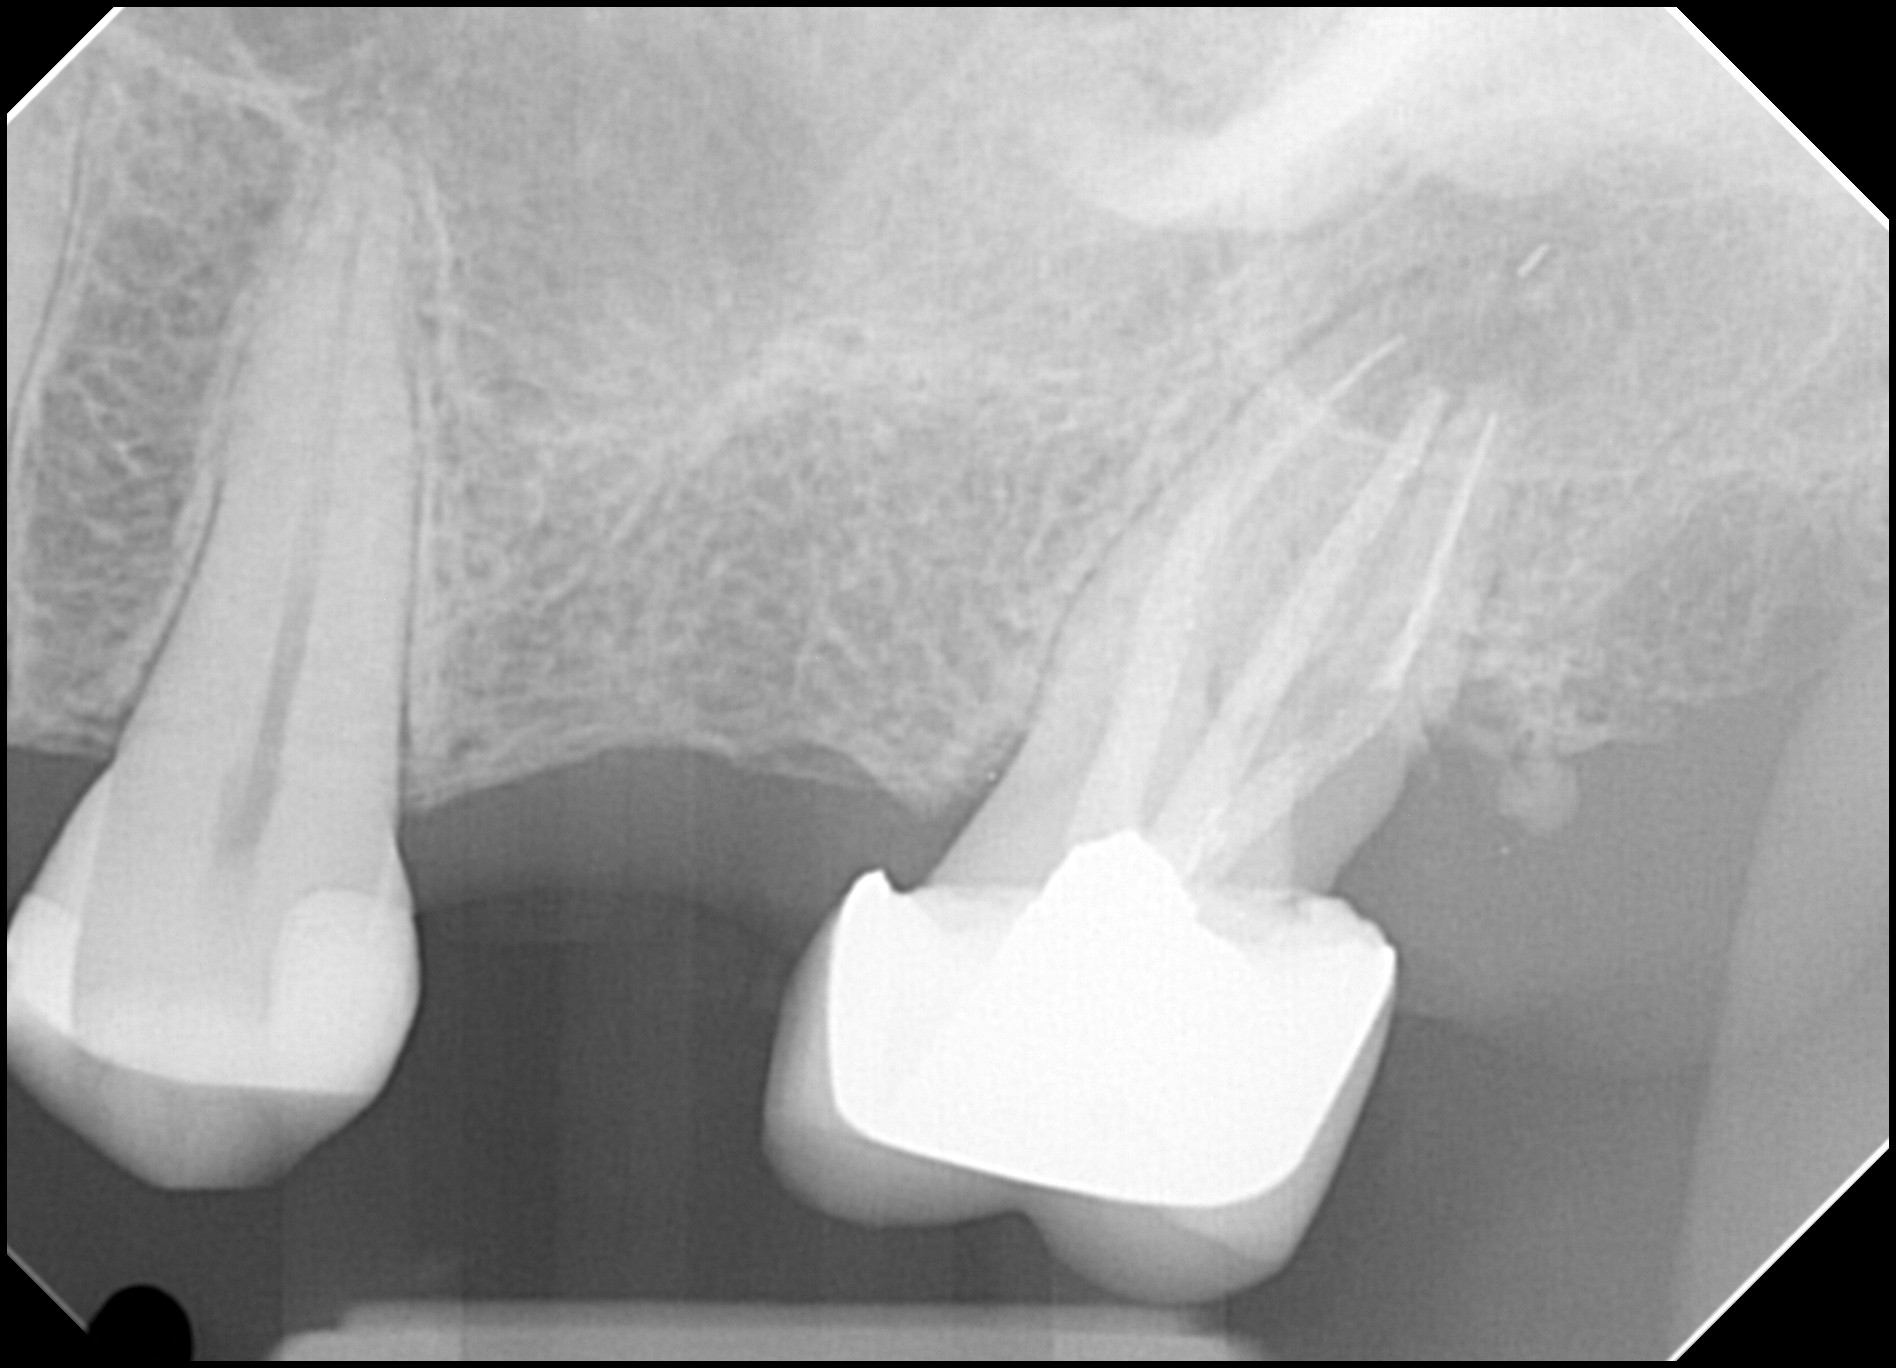

5. What option can be selected for root canal treatment of tooth # 1.5?

6. What option can be selected for root canal treatment of tooth # 1.4?